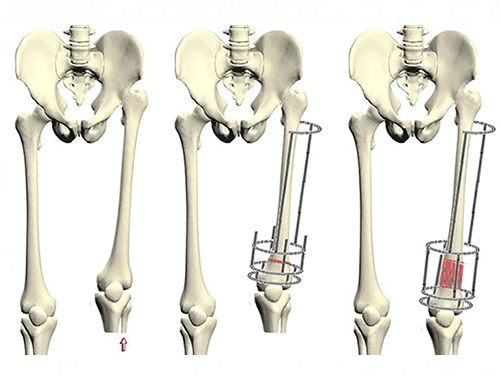

Увеличение длины костей возможно с помощью следующих методов:

- гормональная терапия;

- использование аппарата Елизарова и другие подходы.

Гормональные препараты имеют высокую стоимость и не обеспечивают быстрого роста костей. Чаще всего пациентам приходится использовать их на протяжении всей жизни.

Методика Елизарова включает перелом костей пациента и механическое удлинение костных структур.